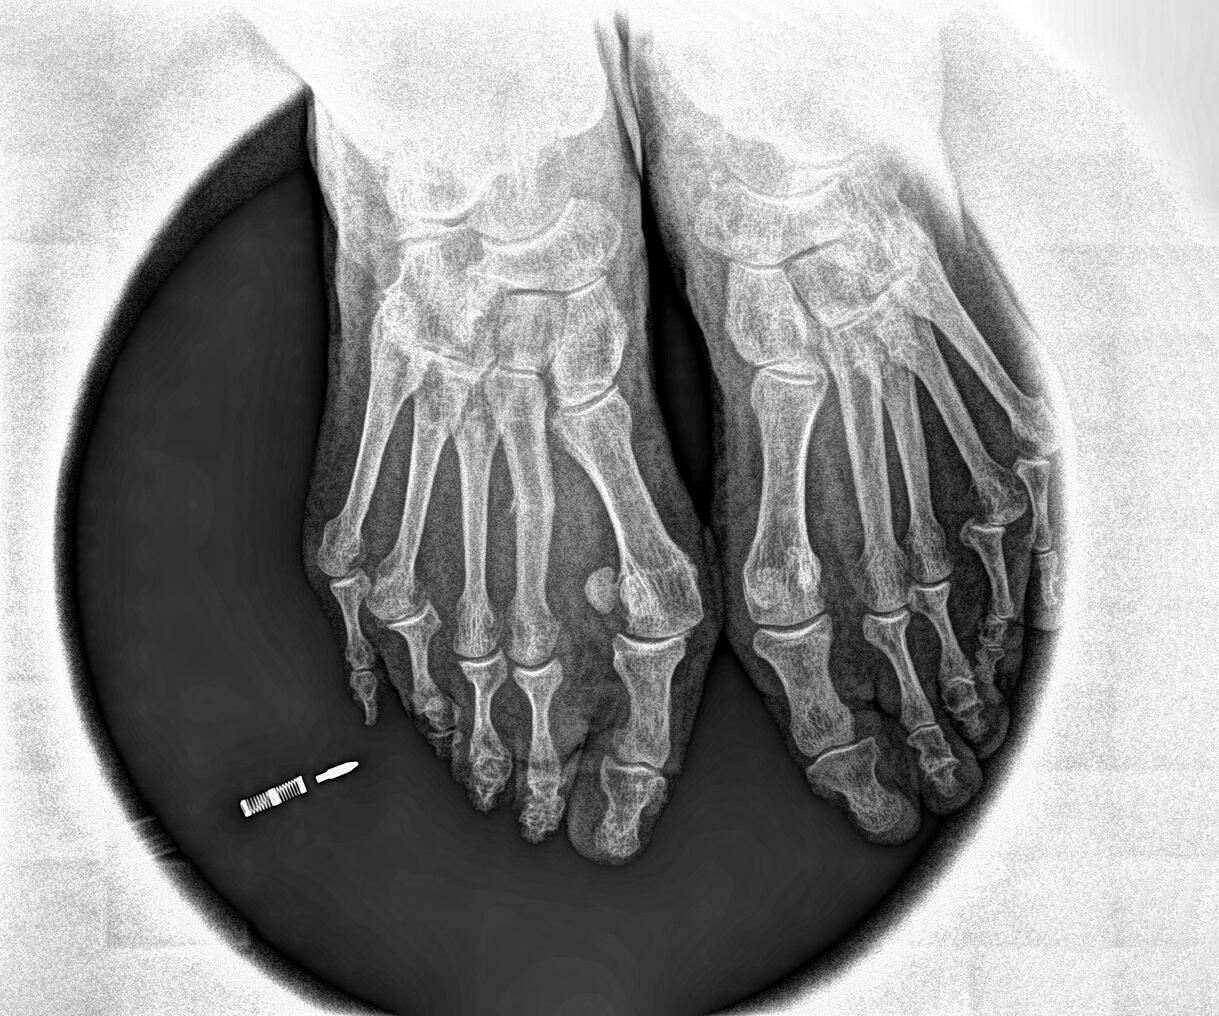

4. Fractura de Estrés (Hallazgo Clave)

- Hallazgo clave en este caso: Tras una radiografía y resonancia, se confirma una fractura de estrés en el segundo metatarsiano, relacionada con:

- Osteopenia + déficit de vitamina D (que debilita el hueso).

- Sobrecarga por aumento brusco de actividad (la caminata de 10 km fue el desencadenante).